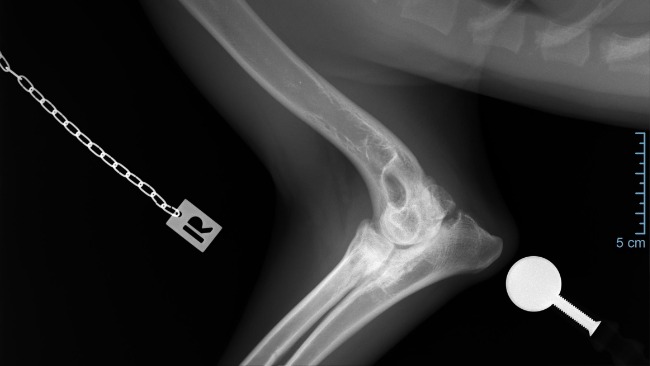

Późniejsze badanie RTG w katowickiej przychodni weterynaryjnej potwierdziło najgorsze obawy – stan łokci jest bardzo poważny, choć Axel nie wykazuje oznak bólu, co dziwi każdego specjalistę.

RTG + GT:

Łokcie – obustronnie, wyraźna inkongruencja, wyraźna podchrzęstna skleroza, cechy OA, UAP

Z weterynaryjnego na nasze: Cechy radiologiczne (Zmiany na RTG) pokazują:

OA - Artroza łokcia u psa to przewlekłe schorzenie zwyrodnieniowe stawu, prowadzące do bólu, sztywności i ograniczenia ruchu, spowodowane uszkodzeniem chrząstki i zmianami w kościach, często wynikające z dysplazji (np. niezrośnięty wyrostek dodatkowy - UAP)

• UAP: Ubytek kości podchrzęstnej w przyśrodkowej części bloczka kości ramiennej, czasem z wolnym fragmentem kostnym.

DIAGNOZA: ED – 3. Stopień

• ED (Elbow Dysplasia): Dysplazja stawu łokciowego, wada rozwojowa, która powoduje zaburzenia w budowie i funkcjonowaniu stawu.

• 3. stopień (ED 3/3): Określa najcięższą formę tej dysplazji, czyli ciężką dysplazję.